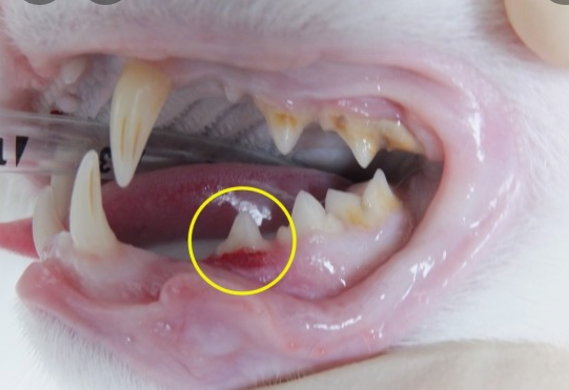

1) 치아 뿌리 흡수 : 치아의 뿌리가 흡수되어 치아가 쉽게 부러지거나 빠진다.

2) 치아 발치 : 심각한 경우에는 치아를 발치한다.